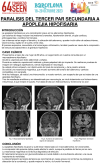

PARALISIS DEL TERCER PAR SECUNDARIA A APOPLEJIA HIPOFISARIA

JUAN ANTONIO MASCUÑANA CALLE; PALOMA GONZALEZ LAZARO; MARIA ZHAO MONTERO BENITEZ; PEDRO JIMENEZ TORRECILLA; MARIA SÁNCHEZ CRESPO JUAREZ; MARÍA AMPARO LOMAS MENESES; FLORENTINO DEL VAL ZABALLOS; FRANCISCO GOMEZ ALFARO; INES GOMEZ GARCIA; MARIA LOPEZ IGLESIAS;